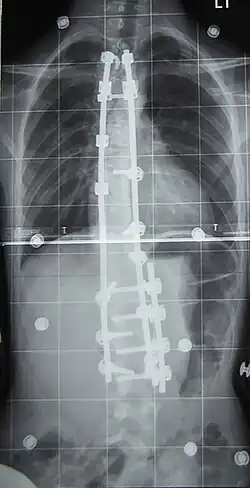

Surgery is usually recommended by orthopedists for curves with a high likelihood of progression (i.e., greater than 45–50° of magnitude), curves that would be cosmetically unacceptable as an adult, curves in people with spina bifida and cerebral palsy that interfere with sitting and care, and curves that affect physiological functions such as breathing.[104][105]

Surgery is indicated by the Society on Scoliosis Orthopaedic and Rehabilitation Treatment (SOSORT) at 45–50°[4] and by the Scoliosis Research Society (SRS) at a Cobb angle of 45°.[106] SOSORT uses the 45–50° threshold as a result of the well-documented, plus or minus 5° measurement error that can occur while measuring Cobb angles.[106]

Surgeons who specialize in spine surgery perform surgery for scoliosis. To completely straighten a scoliotic spine is usually impossible, but for the most part, significant corrections are achieved.[107]

The two main types of surgery are:[108]

- Anterior fusion: This surgical approach is through an incision at the side of the chest wall.

- Posterior fusion: This surgical approach is through an incision on the back and uses metal instrumentation to correct the curve.

One or both of these surgical procedures may be needed. The surgery may be done in one or two stages and, on average, takes four to eight hours.

In 1962, the American orthopaedic surgeon Paul Harrington introduced a metal spinal system of instrumentation that assisted with straightening the spine, as well as holding it rigid while fusion took place. The now obsolete Harrington rod operated on a ratchet system, attached by hooks to the spine at the top and bottom of the curvature that, when cranked, would distract—or straighten—the curve. The Harrington rod obviates the need for prolonged casting, allowing patients greater mobility in the postoperative period and significantly reducing the quality of life burden of fusion surgery. The Harrington rod was the precursor to most modern spinal instrumentation systems. A major shortcoming was that it failed to produce a posture wherein the skull would be in proper alignment with the pelvis, and it did not address rotational deformity. As the person aged, there would be increased wear and tear, early onset arthritis, disc degeneration, muscular stiffness, and acute pain. "Flatback" became the medical name for a related complication, especially for those who had lumbar scoliosis.[119]

In the 1980s, Cotrel–Dubousset instrumentation improved fixation and addressed sagittal imbalance and rotational defects unresolved by the Harrington rod system. This technique uses multiple hooks with rods to give stronger fixation in three dimensions, usually eliminating the need for postoperative bracing.[120]